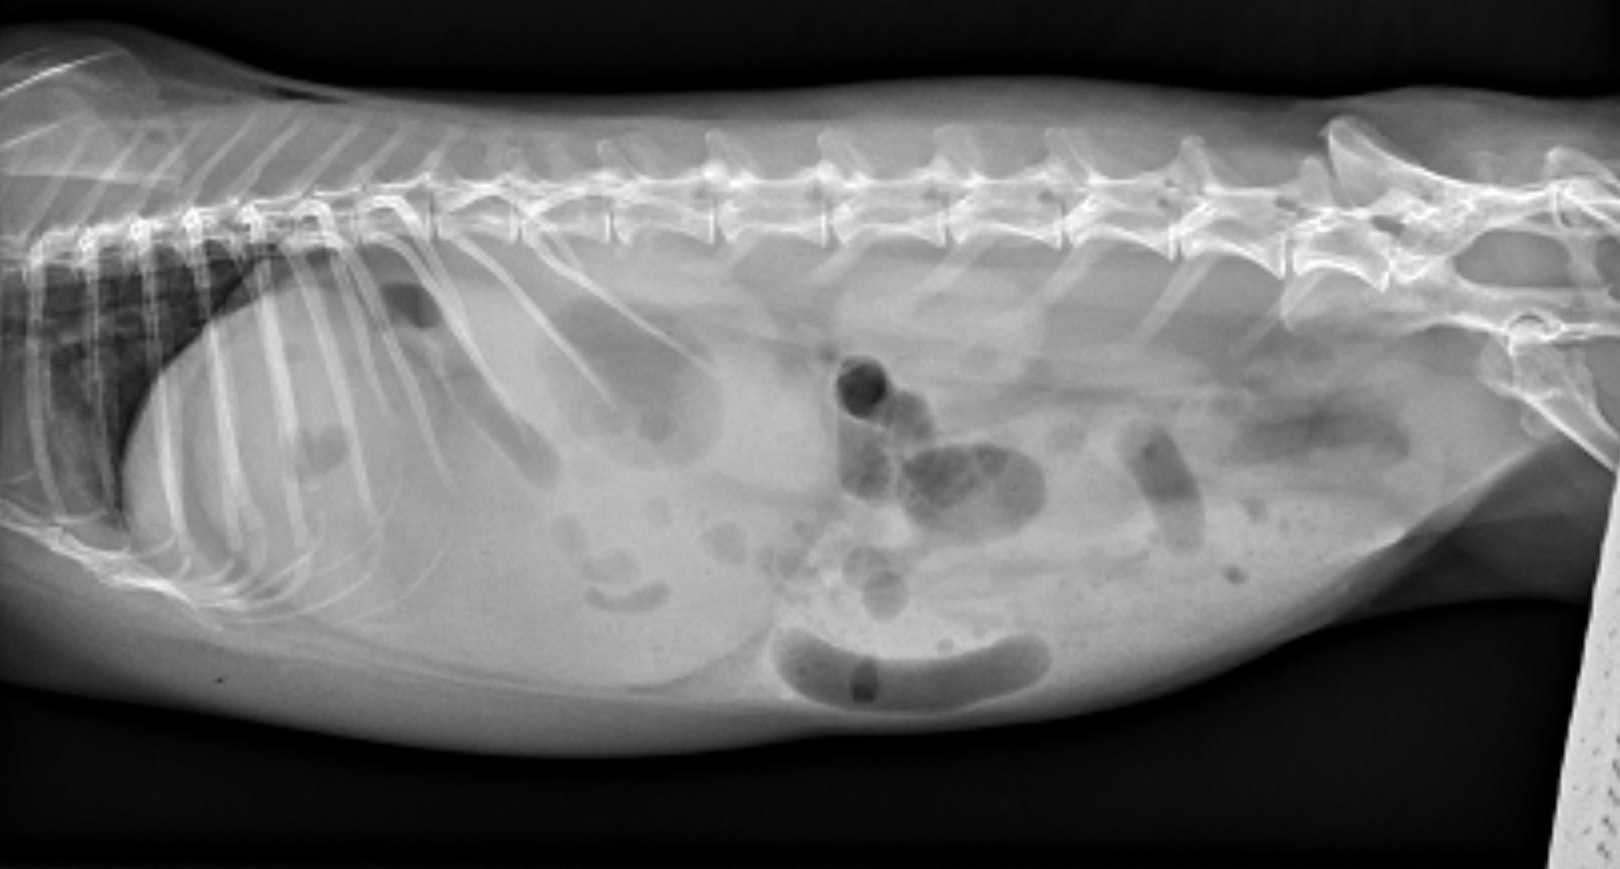

Image shows a right lateral abdominal radiograph of a rabbit with a distended stomach and two populations of bowel consistent with a gastric outflow obstruction.